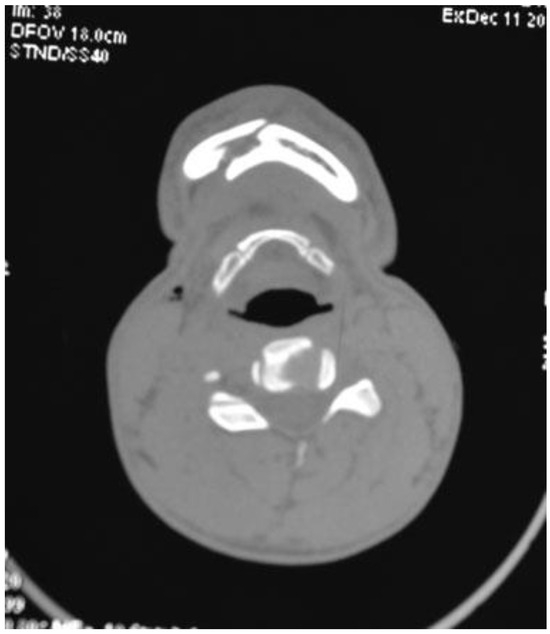

Figure 7. Case 1: Postoperative CT scan of axial section showing interforaminal mandible fracture reduced and fixed with a headless compression screw.

Figure 9. Case 2: Postoperative CT scan of axial section showing interforaminal mandible fracture reduced and fixed with a headless compression screw.